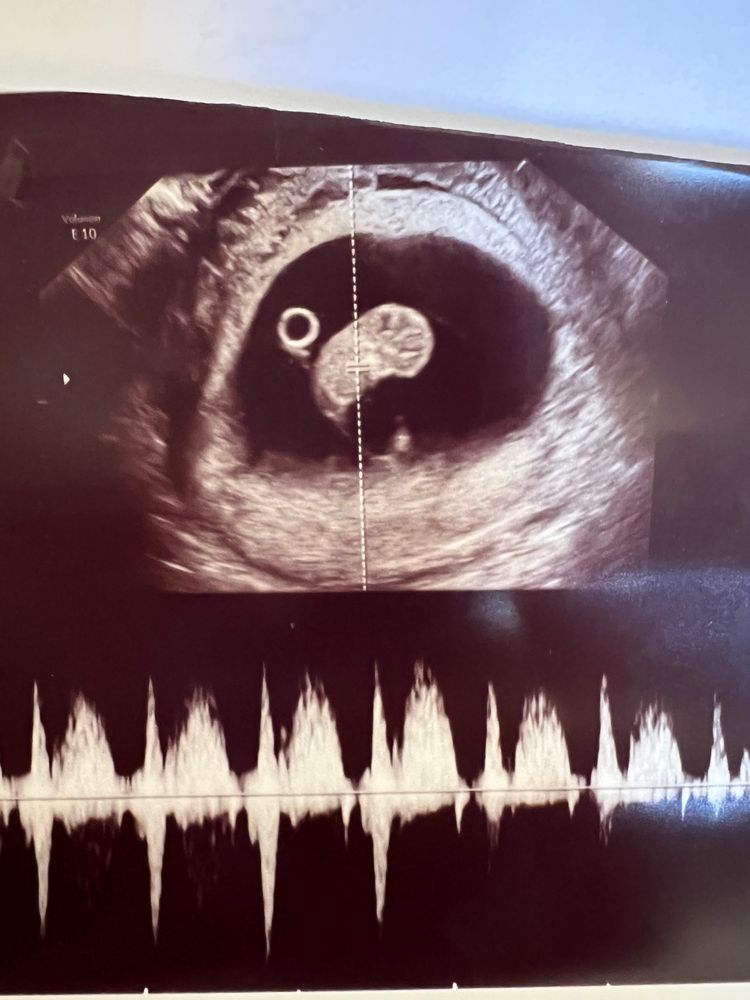

9 недель. Результаты анализов

Вторая встреча с малышом 🥰

Изображение

Вырос! Рост соответствует нормам. Анализы все хорошие, кроме ттг и всех показателей щитовидки 😔 буду пересдавать 27-го. Первый скрин